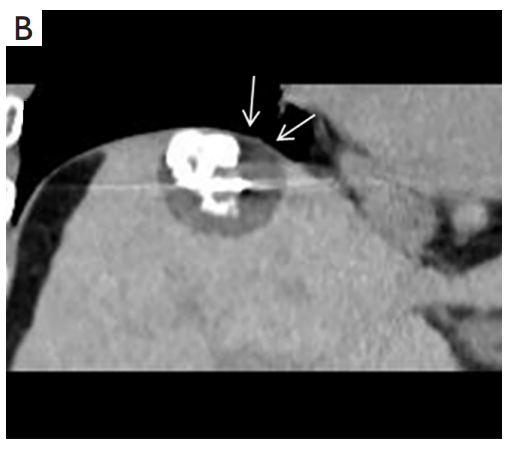

背景:肝癌是中國(guó)最常見的惡性腫瘤之一,發(fā)病率和死亡率都很高。雖然手術(shù)切除是最好的治療方法,但大多數(shù)患者處于晚期或直到住院才有手術(shù)指征。對(duì)于單個(gè)腫瘤直徑小于5厘米的患者,微創(chuàng)治療與手術(shù)切除效果相當(dāng);多個(gè)病灶小于3個(gè),單個(gè)病灶最大直徑小于3cm;不侵犯血管、膽管、鄰近器官和遠(yuǎn)處轉(zhuǎn)移。雖然一些傳統(tǒng)消融技術(shù)方式可以使部分患者受益,但不適用于特殊部位肝癌(定義為毗鄰大血管、肝外臟器和重要結(jié)構(gòu)的腫瘤)的治療。冷凍消融作為一種相對(duì)較新的治療方式,具有明顯的冰球效果、療效好、激活抗腫瘤免疫、并發(fā)癥發(fā)生率低等優(yōu)點(diǎn),尤其適用于特殊部位肝癌患者的治療。我們的研究目的是探討CA治療特殊部位肝癌的安全性、可行性和有效性。

① 在我們的研究中,技術(shù)成功率為100%。動(dòng)態(tài)增強(qiáng)MR檢查隨訪1個(gè)月,66例患者首次技術(shù)有效率為65例(98.5%),MR影像學(xué)未發(fā)現(xiàn)外周臟器損傷。中位隨訪時(shí)間14個(gè)月(范圍2-28個(gè)月)。高危部位肝癌局部腫瘤進(jìn)展率曲線:6、9、15和24個(gè)月的累積局部腫瘤進(jìn)展率分別為10.2%、16.5%、20.9%和30.5%。